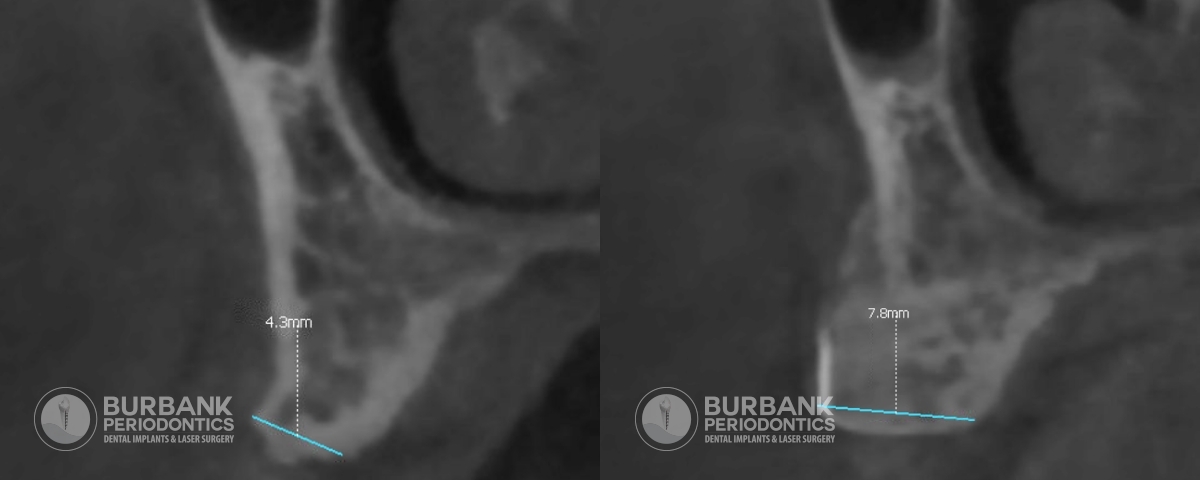

Patient 1

Ridge augmentation is a surgical procedure that regrows lost bone in the jaw after tooth loss. It allows for dental implants to be placed, to replace a missing tooth or teeth, where it would otherwise not be possible. It can also improve the appearance of the teeth in some cases. This procedure is performed with a bone graft, which becomes your own bone over time. It helps reshape the ridge, allowing for a more natural and aesthetically pleasing look, and most importantly, better function.